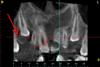

zybnaya feya Опубликовано 1 июля, 2012 Автор Поделиться Опубликовано 1 июля, 2012 Парочка картинок http://s008.radikal.ru/i306/1207/ed/9e2c82c9cf57.jpghttp://s018.radikal.ru/i520/1207/3c/2019b979048e.jpghttp://s018.radikal.ru/i514/1207/fa/77cd86ee79cf.jpghttp://s45.radikal.ru/i107/1207/ad/559fe93e2838.jpghttp://s03.radikal.ru/i176/1207/4a/f38bac89f339.jpghttp://s017.radikal.ru/i420/1207/0e/13921e573948.jpghttp://i009.radikal.ru/1207/ac/8dfb42251c4a.jpghttp://s011.radikal.ru/i317/1207/c4/7126a21a70fb.jpg Кроме наружной резорбции ничего в голову не лезет. Зуб витален. Все пробы отрицательные. Ссылка на комментарий

kriokov Опубликовано 1 июля, 2012 Поделиться Опубликовано 1 июля, 2012 (изменено) скачал кт, чудес у пациентки хватает. Резорбция 21 большая с переходом на боковой периодонт с медиальной поверхности ( может от туда и начинался процесс), + ретенированный клык справа , коронка вестибулярно и фолликулярная (зубосодержащая) киста вокруг его коронки, чего с 21 делать не знаю, (удалять скорее всего), а клык несмотря на кистозное образование надо вытаскивать в зубную дугу.по поводу диагноза 21- только предположительно МКБ -10 К03-3 патологическая резорбция зуба Изменено 1 июля, 2012 пользователем kriokov Ссылка на комментарий

Каплан Опубликовано 1 июля, 2012 Поделиться Опубликовано 1 июля, 2012 Я за наружную резорбцию. 1. Затронута цементноэмалевая граница2. Витальность зуба допустима при наружках. 3. При таком объеме вероятнее всего зуб на выход. Ссылка на комментарий